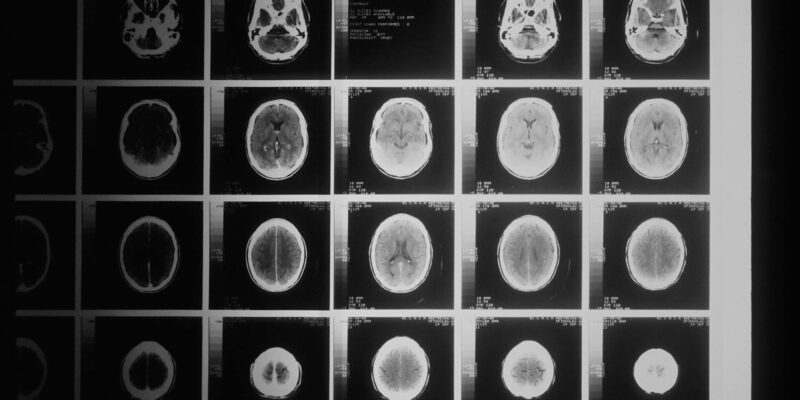

Relata que a ex-servidora da Prefeitura de Cuiabá, já estava aposentada em 2017, quando começou a sentir fortes dores de cabeça. Após ser submetida a diversos exames clínicos, foi diagnosticada com tumor cerebral maligno. Diante de tal quadro clínico, informa que sua cliente foi submetida a uma delicada cirurgia para abertura de seu crânio e extração do tumor que se alojava ali.